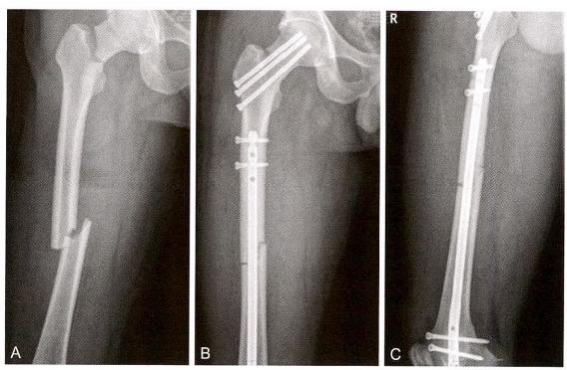

股骨多段骨折,伴股骨转子间、转子下骨折,LambirisⅡ 型(图12-8)。

图12-8 股骨干多段骨折伴股骨转子间、转子下骨折,Lambiris Ⅱ型。A.术前X 线片;B.术前三维CT

透视下见髋内翻,外侧皮质张口,侧位见转子下骨折块前后劈裂移位,外侧经皮钳夹复位转子下骨折块(图12-10)。

图12-10 复位。A.经皮纠正髋内翻;B.侧位见骨块前后移位;C. 经皮钳夹复位后正 位;D.经皮钳夹复位后侧位

经大转子向股骨颈方向钻入一枚直径3.5 mm 的克氏针开展joystick 技术,紧贴后方骨皮质,避免影响近端钉道,内收、内旋髋关节,有利 于暴露大转子顶点。经大转子顶点钻入导针,侧位导针方向略偏前,近 端扩髓后插入导针(图12-11)。

图12-11 撬拨。A.内收、内旋髋关节;B.插入导针,侧位显示导针位置良好;C. 正 侧位显示导针位置良好;D.导针通过粉碎骨折段

利用“复位手指”器或者直径最小的髓内钉来控制导针的插入,股骨 远断端由于重力和小腿三头肌的牵拉而向后移位,通过经皮撬拨抬高远 端,使导针紧贴前方皮质插入股骨髁(图12-12A-G)。 术中采用经皮钳 夹、经皮撬拨和joystick 技术。

图12-12 扩髓插钉。A. 插入髓内钉;B.用髓内钉进行撬拨复位;C.侧位显示远端骨 块向后成角移位;D. 撬拨复位+joystick 技术复位移位段;E. 插入导针达远端髓腔内, 正位;F.导针达远端髓腔,侧位;G.术中照片

(4)第四步:近远端锁定。近端经股骨颈锁钉固定后,远端徒手植 入3枚锁钉,多平面固定微创手术切口(图12- 13)。

图12-13 近远端锁定。A. 近端经导向架植入导针;B. 近端头颈部用2枚螺钉锁定;C. 远端用3枚螺钉锁定;D.远端侧位透视示螺钉位置正确;E. 术中照片显示微创闭合 复位